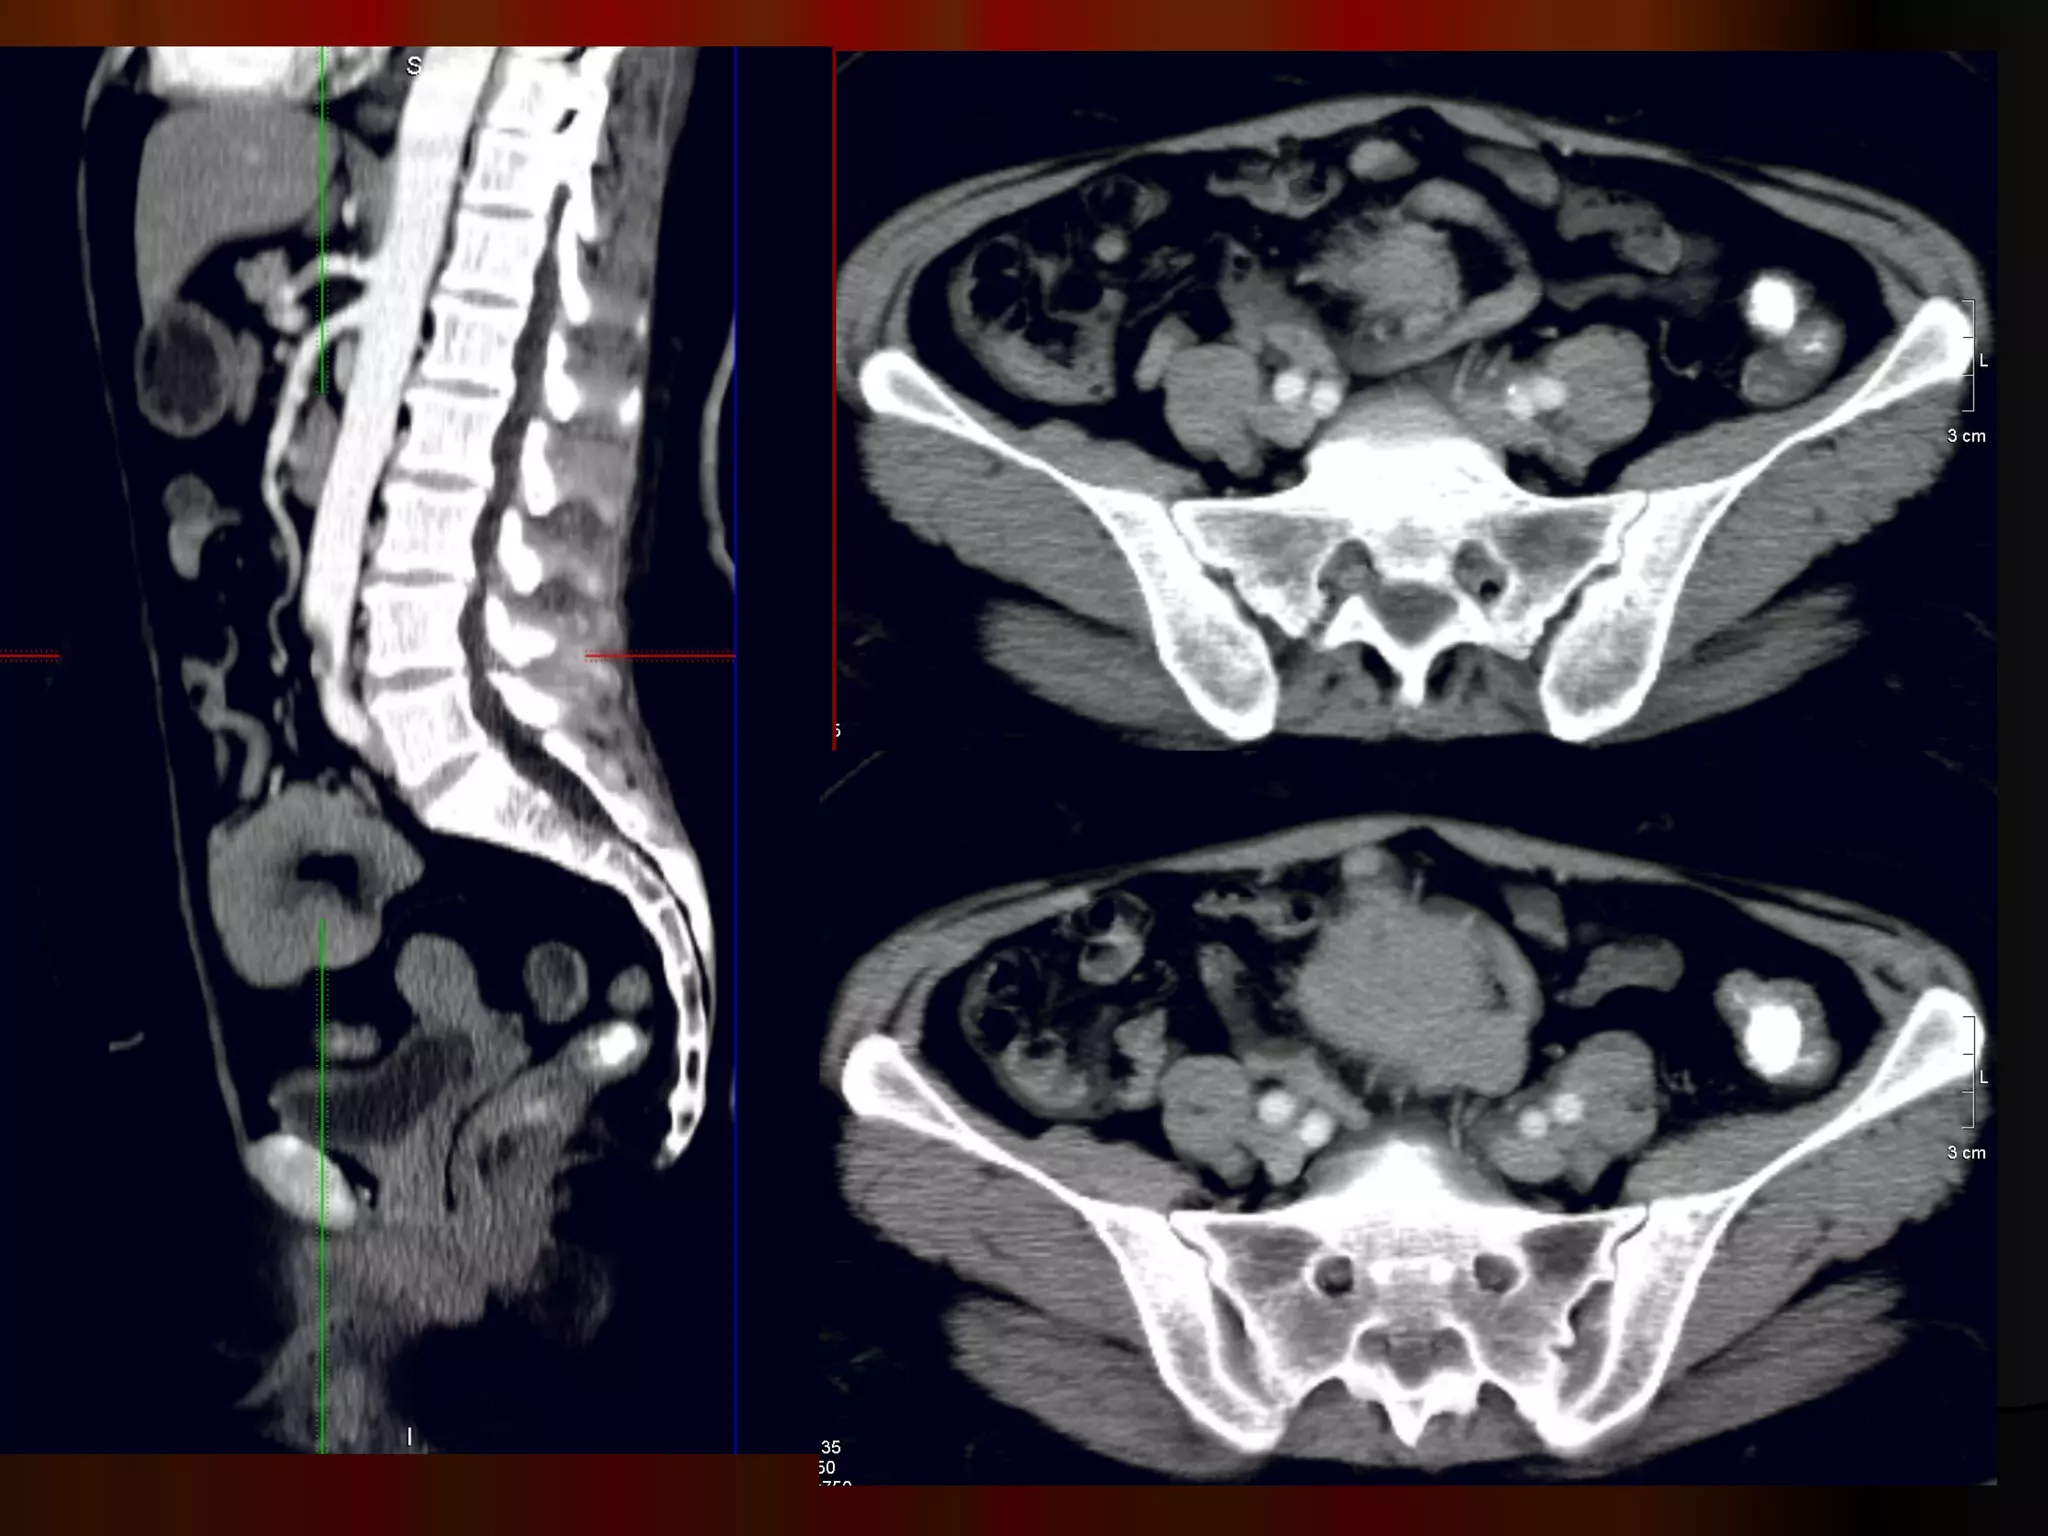

Женщина, 70 лет,боли в эпигастрии, анемия, резкая потеря веса Случай 4.

Инфильтративная форма ракажелудка с региональным прорастанием, метастазы в яичники ( рак Крукенберга) и параректальную клетчатку ( Шницлеровский метастаз)

Женщина, 70 лет, боли в эпигастрии, анемия, резкая потеря веса Случай 4.

Инфильтративная форма рака желудка с региональным прорастанием, метастазы в яичники ( рак Крукенберга) и параректальную клетчатку ( Шницлеровский метастаз)